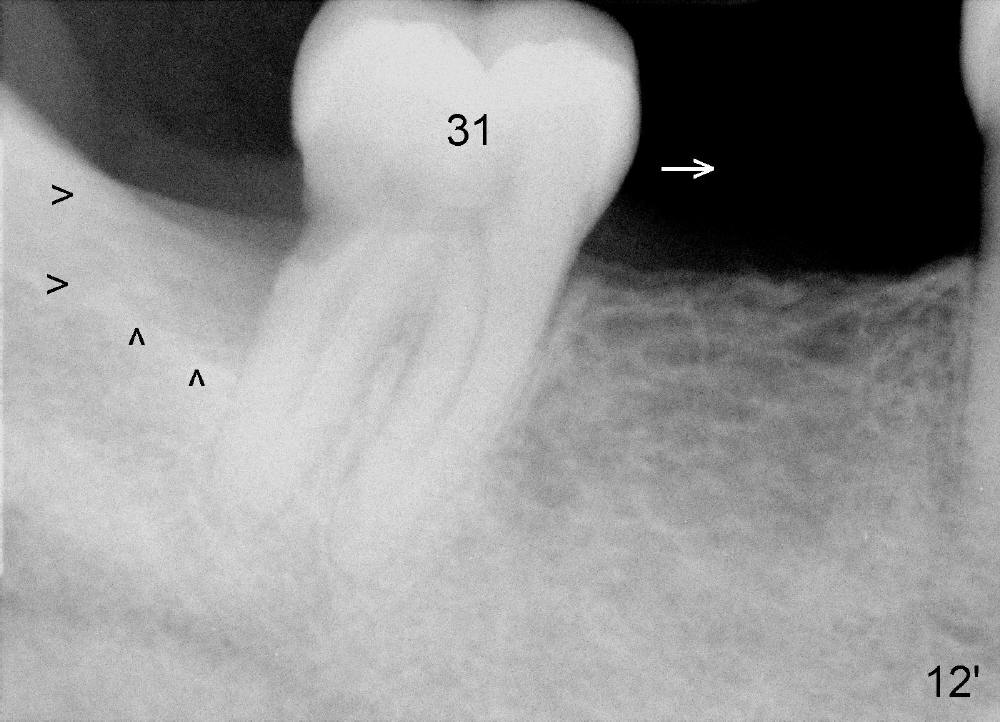

| Fig.12': Preop, #31 shifts mesially (white arrow). There is a large bony defect distally (black >). | Fig.12: 9 months postop. The distal bony defect decreases (black >) as #31 distalizes. Return to original article |